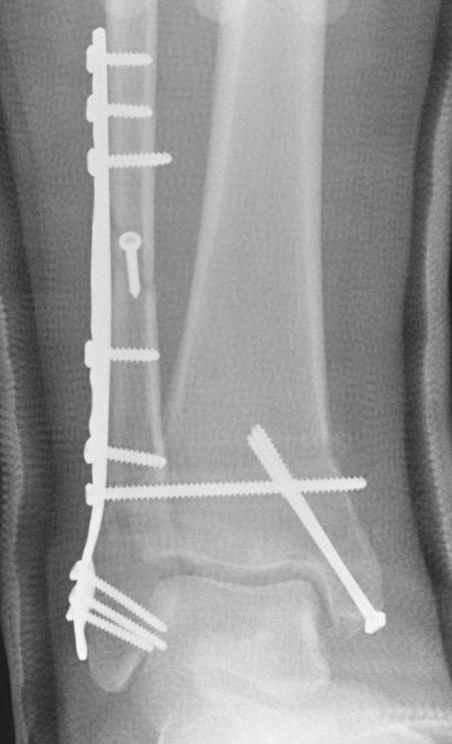

Если до сих ничего не сделано, с артродезом сустава в данный момент я бы повременил, на выставленных январских снимках хорошо сохранившийся сустав, а в "мортиз" (трехчетвертной) и на боковых снимках не менее 5 мм укорочение малоберцовой кости. Косые переломы лучше фиксировать пластинами, как то мы разбирали случай, где было отмечено, что это закон "таранная кость всегда следует за малоберцовой".

В данном случаи я бы уговорил больного на реконструкцию, для этого после удаления шурупов, спереди очистить от рубцов синдесмоз, несросшуюся наружную лодыжку - остеотомия по линии перелома и компрессирующий (lagging technique) кортикальный шуруп 3.5 мм по поперечнику остеотомии. Следующий этап - восстановление длины малоберцовой за счет удлинения, сделать поперечную остеотомию где-то на уровне сантиметр выше вашего синдесмозного шурупа, наложить длинную пластинку, прикрепить пластину за дистальный конец двумя или тремя шурупами; сохраняя контакт пластины с костью, имеющимся

compression&tension device AO system (при отсутствии любой lamina spreader подойдет, создать дистанцию между пластиной и шурупом, проведенным проксимальнее пластины) толкая проксимальный отдел пластины, низвести пластину, мортиз рентгенограмма подскажет на сколько. Если заранее сделать предоперационный план (ренгенограмма другой стороны), тогда точно можно определить, на сколько вам необходимо сделать поперечную остеотомию малоберцовой кости, для закрытия создавшегося дефекта.

Убедившись, что желаемая длина восстановлена, окончательная фиксация пластины, при этом через пластину пару 3.5 мм шурупов на синдесмоз, предпочтительно в четыре кортекса и оставить на 3 мм длиннее, если под нагрузкой синдесмотический шуруп сломается, сломанный конец легче удалить с медиальной стороны.

Медиальная сторона не в нагрузочной зоне, и там большая дыра - если есть 2.7 мм шурупы, или пару спиц в ваших условиях или методика Лазарева. Необходимо уделить внимание к мягким тканям, обнажается кость с латеральной стороны и у места где проводится остеотомия.

После 5-6 недели после травмы сделана повторная операция, обошлись без удлинения малоберцовой.